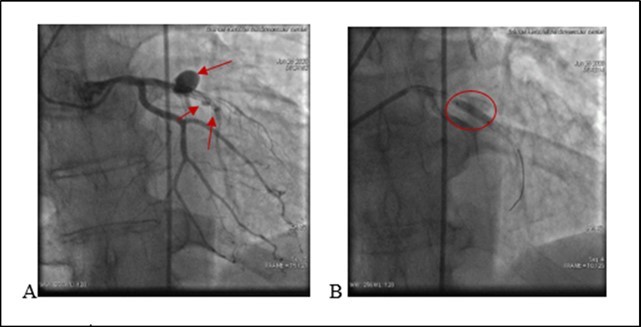

21.06.20 05:03 Am the patient complained chest pain. A drop in blood pressure and bradycardia was noted. T/A 80/60 mm Hg. There was no changes on echocardiography. No pericardial separation. No ST segment changes on ECG . Due to hemodynamic instability we decided to repeat a coronary angiography and it again revealed a medial segment stent thrombosis in LAD with multiple extravasations at proximal and medial segments Type III and II (see. Figure 3) -late perforation of coronary artery. At proximal segment pericardial hemorrhage provided pericardial hematoma with diameter 9-10 mm. At medial were visualized. During coronary angiography a patient’s condition deteriorated. Blood pressure dropped to T/A 60/40 mm Hg. A cardiac tamponade developed because of blood leak into pericardial space. A 3 mm balloon was inflated immediately in the site of rupture, with complete occlusion of vessel, stopping of a blood flow in the LAD and termination of extravasation into the pericardial space.

Figure 3.A. (21.06.2020) Second acute stent thrombosis and perforation Type III and II (red arrows) B. Balloon inflation in the site of rupture (red circle).

Deployment of covered stents was not purposeful due to highly suspected infection. A decision was made for urgent surgical treatment. A patient was urgently transferred to a cardiac operation theater surgical department with inflated balloon to eliminate a blood leakage in the pericardium. Ligating the coronary artery with removing stents, subsequent bypass grafting was performed, with removal of 500 ml of coagulated blood from the pericardial space. Post-surgery period remained stable. Leukocytes - 14.24 x10`3/μ L (N 4-10). A Pseudomonas Aeruginosa (multirresistent) - was positive after coronary wall tissue histomorphological examination. During hospitalization developed renal insufficiency.